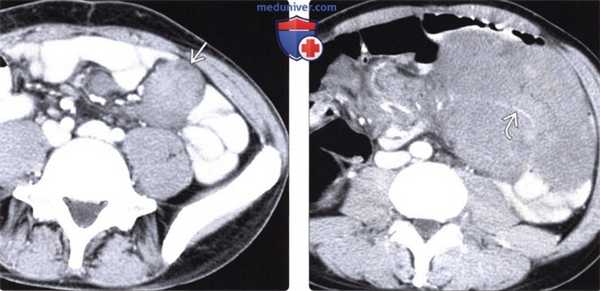

(Слева) На аксиальной КТ с контрастом у пациента с синдромом Гарднера визуализируется небольшое мягкотканное образование в брыжейке - типичная десмоидная опухоль, никак не проявляющаяся, вследствие чего она не была оперативно удалена.

(Справа) На аксиальной КТ с контрастным усилением у этого же пациента 8 месяцев спустя обнаруживается, что опухоль в значительной степени увеличилась в размерах, обрастает брыжеечные сосуды и кишечник. Пациенту потребовалась тотальная резекция тонкой кишки с брыжейкой и пересадка тонкой кишки.